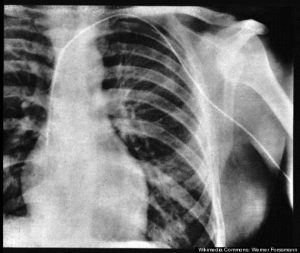

यादरम्यान त्यांनी स्वतःवर कॅथेटरचा प्रयोग करून पाहिला. त्यांची अशी धारणा होती की, हृदयात जर का कॅथेटर घालता आला तर त्याचा उपयोग करून इन्ट्राकार्डिअॅक प्रेशर (हृदयाच्या विविध कप्प्यांमधील दाब) मोजता येईल व कॅथेटरद्वारा रंगद्रव्ये (radio-opaque dye) शरिरात सोडून त्याची एक्स-रे प्रतिमा घेता येईल. फोर्समान यांनी बरेच प्रयत्न करूनही त्यांचे म्हणणे ऐकून घेण्यास कोणी तयार होत नव्हते. त्यामुळे सुरुवातीस फोर्समान यांनी मृत मानवी शरिरांवर प्रयोग करून पाहिले. एबर्सवाल्ड येथे काम करीत असतांना त्यांनी स्वतःवरच हा प्रयोग करण्याचे ठरविले. त्यांच्या विभागप्रमुखांचा यास विरोध होता, तिकडे त्यांनी पूर्ण दुर्लक्ष केले. ऑपरेशन थिएटर मधील परिचारिका गेर्डा डिटत्सेनहिला त्यांनी या प्रयोगामध्ये सामील करून घेतले. गेर्डाने, फोर्समान यांना मदत करण्याची तयारी दर्शविली, परंतु तिची एक अट होती. तिचे म्हणणे असे होते की हा प्रयोग तिच्यावरच करण्यात यावा. फोर्समानयांनी सुरुवातीला होकार दिला. त्यांनी तिला ऑपरेशन टेबलवर निजावयास सांगितले. तिला ‘लोकल अॅनस्थेशिया’ देण्याचा बहाणा करून तिला ऑपरेशन टेबलला जखडून टाकले. स्वतःला लोकल अॅनस्थेशिया दिला व कोपरातून कॅथेटर आत घातला. मग त्यांनी गेर्डाला सोडविले व तिला एक्स-रे विभागाला सांगण्यास सांगितले. फोर्समान यांनी जवळजवळ दोन फूट इतका कॅथेटर स्वतःच्या शरिरात घातला होता. एक्स-रे विभाग खालच्या मजल्यावर होता. फोर्समानस्वतः चालत तेथे गेले. तेथे गेल्यावर त्यांनी विभागप्रमुखांचे मन वळविले व कॅथेटरमधून रंगद्रव्ये आत इनजेक्ट केली (सोडली). मग जेव्हा एक्स-रे काढण्यात आला तेव्हा कॅथेटर, फोर्समान यांच्या हृदयात उजव्या बाजूला (राईट व्हेन्ट्रीकुलर कॅव्हिटी मध्ये) आत स्पष्ट दिसून आला.